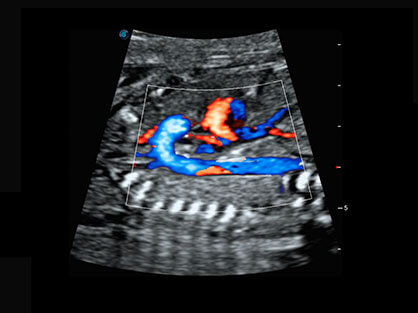

• Wi-Flow

通过对组织运动信息、血流信号及背景噪声进行准确智能的阈值判定,高效提取出微弱血流信号,获得高灵敏度和空间分辨率的血流图像,为临床提供更加真实和丰富的诊断信息。